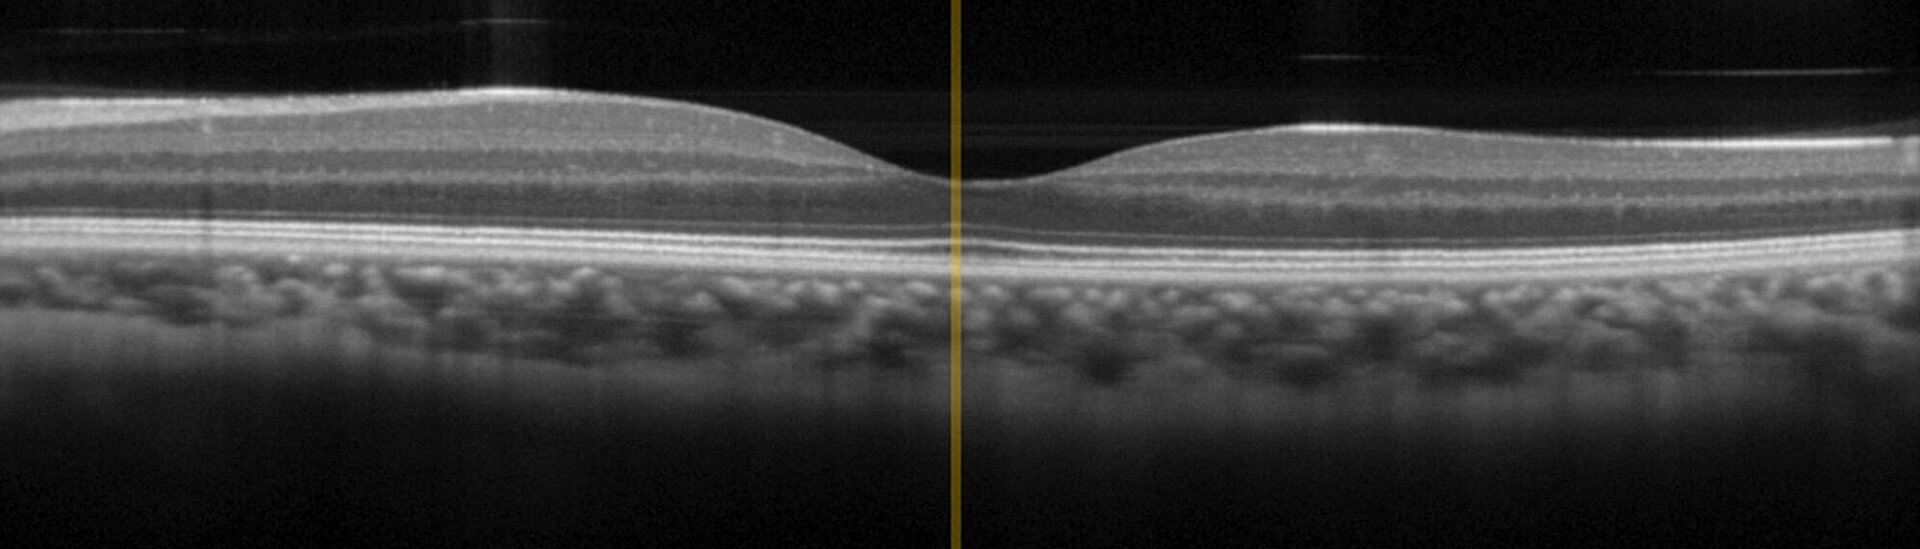

OCT ist ein interferometrisches Bildgebungsverfahren, das auf breitbandigem Infrarotlicht im Wellenlängenbereich zwischen 0,8 µm und 1,4 µm basiert, um das Gewebe optimal zu durchdringen. OCT hat bereits den "Goldstandard" in der Augenheilkunde erreicht, findet aber in letzter Zeit zunehmend auch Anwendung in der Dermatologie, z. B. zur Diagnose von Hautkrebs. Im Vergleich zu herkömmlichen invasiven Diagnosemaßnahmen liefert OCT schnellere Ergebnisse und reduziert Nebenwirkungen und Belastungen für die Patienten.

Die OCT-Technologie verwendet breitbandiges IR-Licht (im Wellenlängenbereich zwischen 800 und 1400 nm, welches am besten in das Gewebe eindringt) mit kurzer Kohärenzlänge in einem Michelson-Interferometer Aufbau. Das Signal ergibt sich aus der Interferenz von Sonden- und Referenzstrahl, die auf Reflexionen an den Brechungsindexgrenzen im biologischen Gewebe beruht.